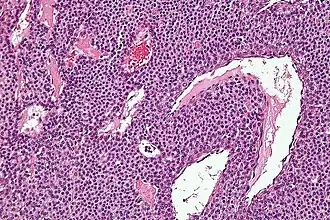

Гломусная опухоль уха (гломангиома) — преимущественно доброкачественное новообразование, развивающееся из клеток параганглиев, ассоциированных с симпатическими и парасимпатическими ганглиями, привязанными к таким анатомическим образованиям как аурикулярная ветвь блуждающего нерва (нерв Арнольда), барабанный нерв (ветвь языкоглоточного нерва, нерв Якобсона), луковица яремной вены.

Наиболее адекватным считается термин параганглиома, так как он соответствует понятию о гистологическом строении данной опухоли и подразумевает общность патогенеза с гомологичными новообразованиями другой локализации, так же развивающихся из параганглионарной ткани — параганглиомами лёгких, кожи, надпочечников (феохромоцитома). Параганглиомы латерального основания черепа ассоциированы с парасимпатическими ганглиями в обилии представленными в этой анатомической зоне.